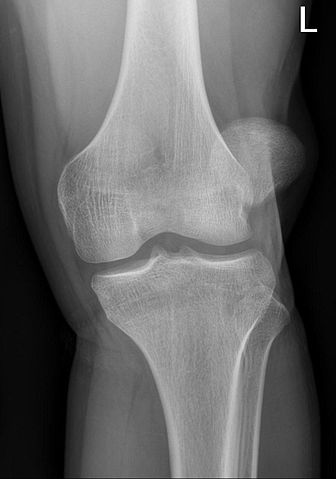

During your consultation, Dr George Awwad will assess your symptoms, review imaging studies such as X-rays and MRI scans, and evaluate alignment metrics such as the TT-TG distance and patellar height. He will provide personalised advice on whether a TTO is appropriate for your condition, and whether it should be performed as a standalone procedure or in combination with other stabilisation techniques.

During your consultation, Dr George Awwad will perform a detailed clinical assessment and review imaging, including X-rays, CT scans, or MRI, to evaluate your alignment and joint condition. Measurements such as the TT–TG distance, patellar height (Caton–Deschamps Index), and trochlear shape will help determine whether TTO is appropriate and whether it should be combined with other procedures such as MPFL reconstruction or cartilage restoration. Dr Awwad will also consider your goals, age, activity level, and overall knee health to provide individualised surgical recommendations.